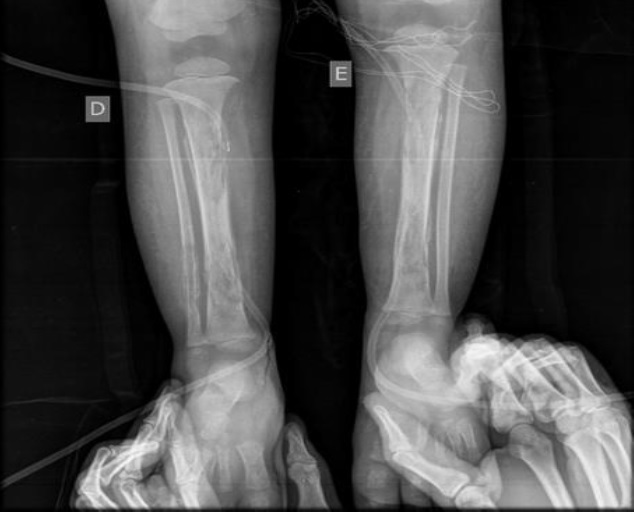

Em ultrassonografia de membros inferiores, foram confirmados abscessos nos pés. Na investigação, foi diagnosticada a osteomielite que acometia úmero, tíbia, ossos dos pés e das mãos bilateralmente. Foi feita drenagem contínua de lojas de secreção purulenta na região das tíbias.

As radiografias confirmaram o diagnóstico de osteomielite (Figuras 1 a 5). Em culturas de secreção tibial, foram isolados Escherichia coliESBL e Proteus mirabilis, sensíveis a imipenem e amicacina. Dessa forma, optou-se por tratamento com antibioticoterapia parenteral, ao longo de tempo prolongado de internação.

Foram realizadas radiografias seriadas e o consequente tratamento cirúrgico de drenagem de abscessos e colocação de drenos. Não foram realizadas cintilografias e ressonância magnética, uma vez que o diagnóstico se fez tardiamente com o quadro já instalado de forma importante. Esses últimos exames contribuiriam para um diagnóstico mais precoce. Não foi realizada biópsia óssea das áreas acometidas, exame eventualmente necessário1. Em alguns casos, radiografias podem estar normais4, porém, em outros, como no caso descrito, elas se apresentam alteradas, conforme visto nas imagens.

Em seguimento ambulatorial, o paciente apresenta padrão radiológico melhor, como evidenciado em radiografia recente, ausente o atraso no crescimento, uma vez que placas epifisárias não se mostram afetadas. Permaneceu em antibioticoterapia estendida por mais cinco meses além do programado na alta hospitalar e isento de complicações novas por osteomielite. Internações devido às crises álgicas ou outros tipos de infecções já foram registradas.